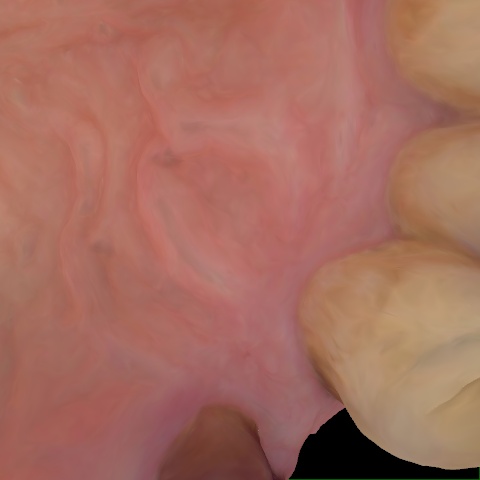

Annotated as "Good"